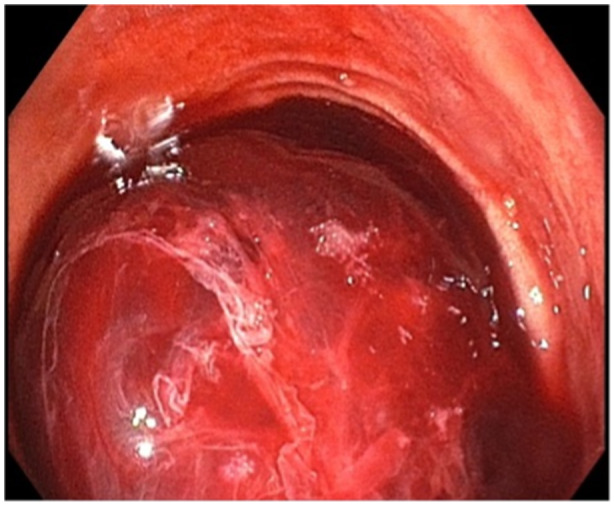

Ectopic varices are defined as portosystemic venous collaterals occurring in the gastrointestinal tract outside of the cardio-esophageal region. Duodenal varices are not routinely encountered by pediatric gastroenterologists. At the time of this case report, there are no consensus guidelines on the management of bleeding duodenal varices in pediatric patients. This is a case of a 14-year-old young woman with a history of multi-visceral transplantation due to short gut syndrome. The patient had developed duodenal varices near her transplant anastomosis, which were incidentally biopsied on endoscopy causing resultant bleeding that required endoscopic hemostasis. This case highlights the need for recognition of duodenal varices as a potential etiology of gastrointestinal bleeding in children and describes band ligation as an effective hemostatic modality.

Abstract Image